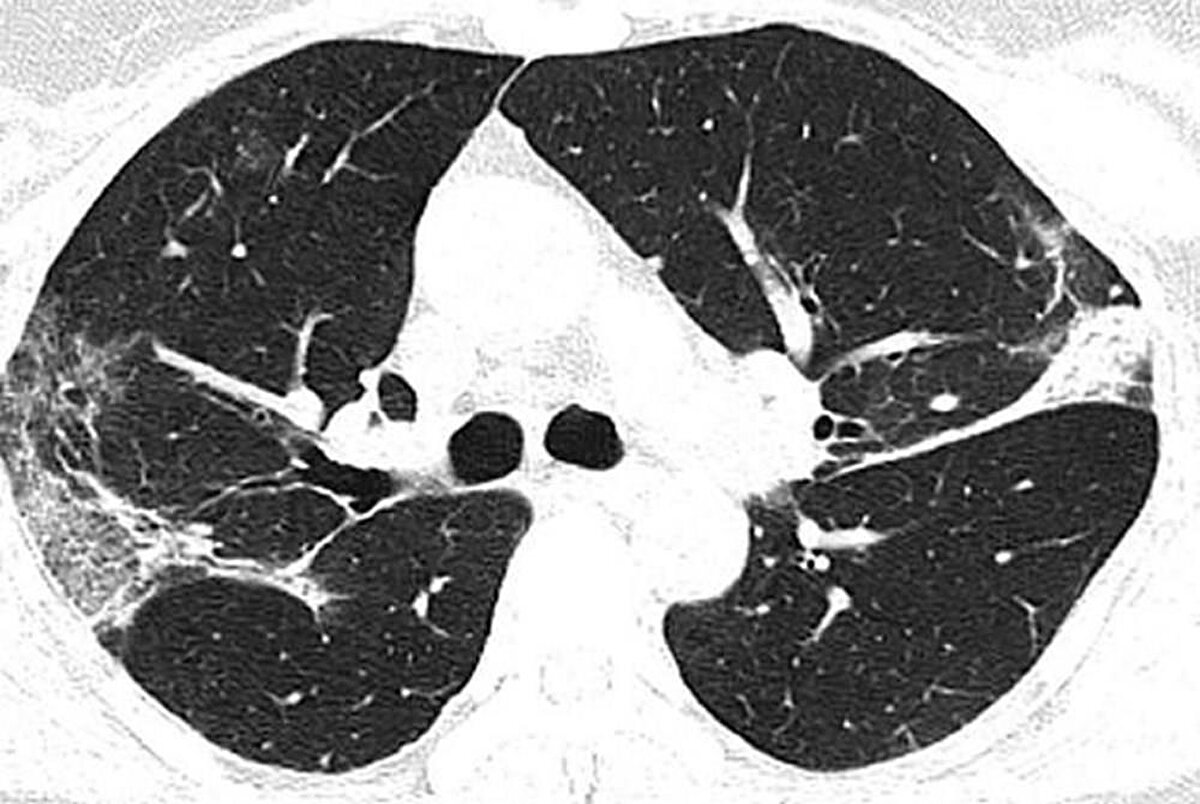

Çin'in Hubey eyaletine bağlı Wuhan'daki salgının kaynağı olduğu düşünülen hayvan pazarında çalışan 44 yaşındaki bir Çinlinin röntgen filmleri yeni tip corona virüsün akciğerlere verdiği zararı açıkça gösteriyor. Filmlerde akciğerdeki hava boşluklarının çoğunluğunun virüs nedeniyle dolduğu görülüyor. Uzmanlar, taramalarda görülen beyaz lekelerin SARS ve MERS'te de mevcut olduğunu belirtti.

Kuzey Amerika Radyoloji Derneği (RSNA), yeni tip corona virüsün (Covid-19) ortaya çıktığı Çin’in Wuhan kentindeki salgının kaynağı olduğu düşünülen deniz ürünleri pazarında çalışan ve 44 yaşında virüs nedeniyle hayatını kaybeden bir adamın röntgen filmlerini kamuoyuyla paylaştı. Filmlerde corona virüsün akciğerleri nasıl tahrip ettiği net bir şekilde görülüyor.

Hava kesecikleri doluyor X-ray ışını taramalarında corona virüsün etkileği yerler beyaz olarak görülüyor. Uzmanlar, hastada virüsün akciğerlerdeki hava keseciklerini kısmen doldurduğunu ve akciğer nodüllerine sebep olduğunu belirtti. .Diğer taraftan aynı tip anormalliklerin SARS (Şiddetli Akut Solunum Sendromu) ve MERS (Ortadoğu Solunum Sendromu) vakalarında da görüldüğünü söylediler.